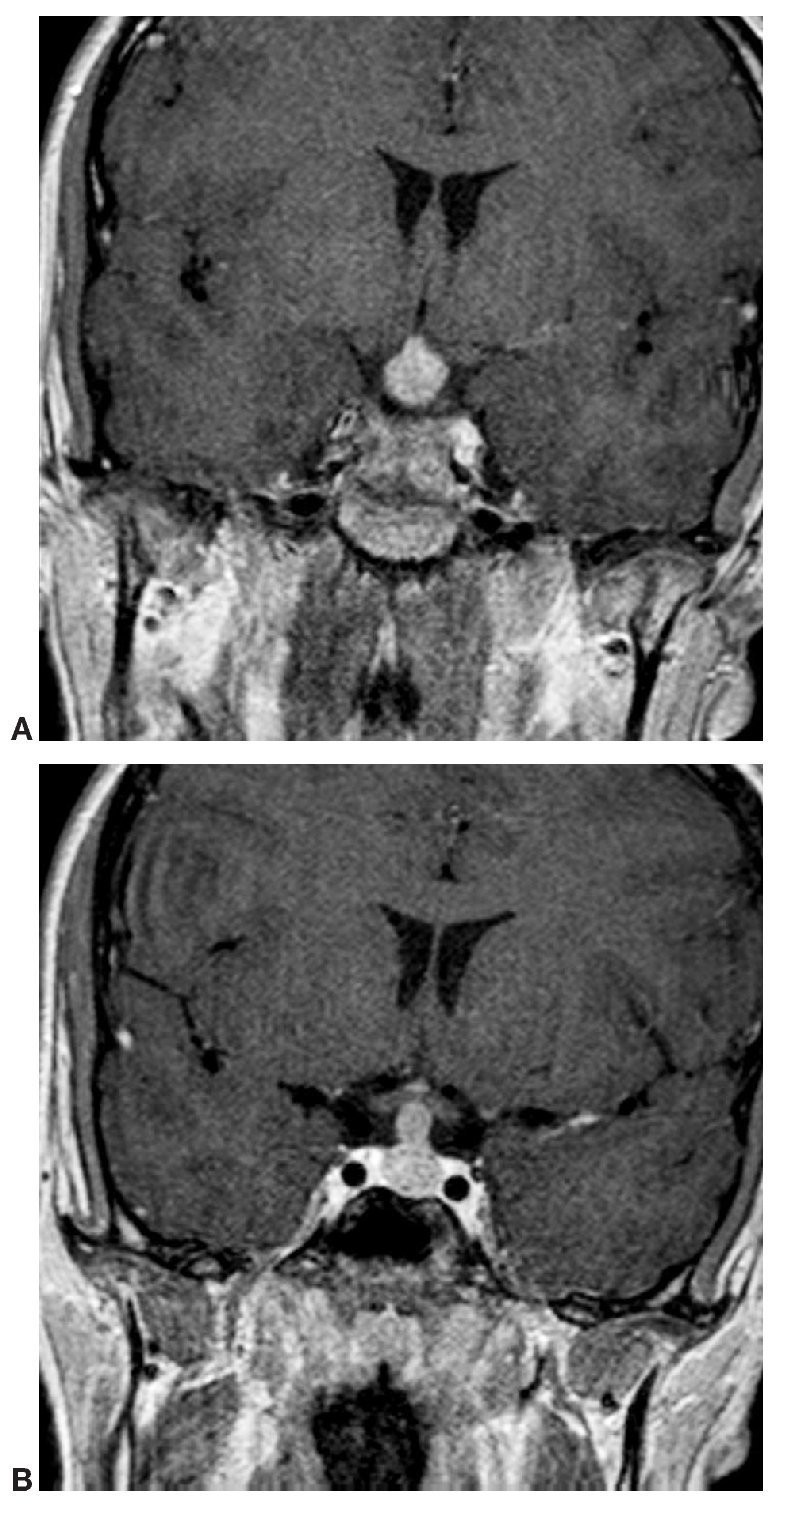

Paciente varón de 14 años de edad, con talla baja y panhipopituitarismo.

Fig. 1.

Fig. 2.

Comentario en las páginas 339-40